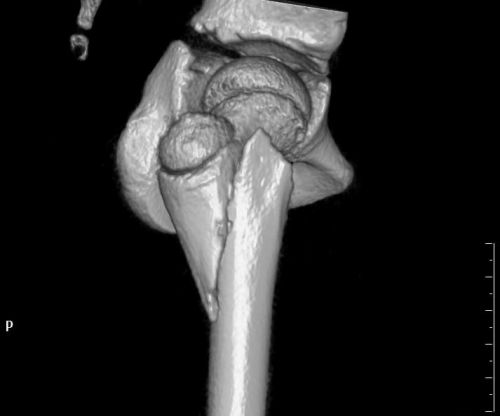

术前检查发现,右侧股骨粗隆间骨折。

医生检查发现,小雨右大腿肿胀、疼痛、伴畸形、活动障碍,全身多处软组织皮肤擦挫伤,X线显示“右侧股骨粗隆间骨折”,需立即手术。在完善相关检查后,儿童骨科肖晟主任医师、李欣副主任医师、曹舒博士等为小雨施行“右侧股骨粗隆间骨折切开复位内固定术”。幸运的是,小米只是臀部肌肉挫伤,经过冰敷等处理已无大碍。